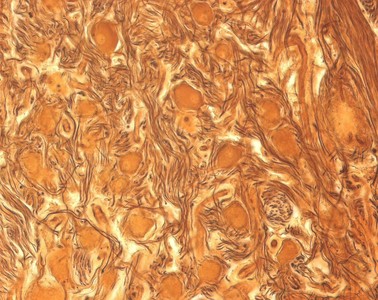

Präparat 27: Multipolare Nervenzellen, Grenzstrangganglion (Rind), Cajal-Versilberung

An diesem Präparat aus einem Ganglion des Grenzstrangs, Truncus sympathicus, sind die Nervenzellen mit der Cajal-Versilberung gefärbt (imprägniert). Wie Sie ja bereits bei Präparat 26 gelernt haben, besitzen Nervenzellen ein Perikaryon und unterschiedliche Fortsätze, die Dendriten und das Axon. Mit der Cajal-Versilberung werden Bestandteile des Zytoskeletts, die Neurofibrillen, tiefbraun bis schwarz angefärbt. Mit dem Elektronenmikroskop lassen sich Neurofibrillen in Neurofilamente und Neurotubuli auflösen. Die Neurofibrillen sind in den Axonen der Nervenzellen viel kompakter zusammengelagert als in den Dendriten und Perikaryen des Neurons. Die Axone erscheinen daher wesentlich dunkler als die Dendriten und die Perikaryen, die gelblich/braun gefärbt werden und nur am Rand versilberte Neurofibrillen zeigen. Der Zellkern der Neurone ist nicht angefärbt und erscheint daher als rundes helleres Gebilde im Perikaryon. Gliazellen (Satellitenzellen), die die Perikaryen umgeben, sind hier nicht eindeutig zu identifizieren.

Der Truncus sympathicus (Grenzstrang) ist Teil des vegetativen Nervensystems und liegt der Wirbelsäule an. Charakteristisch für ein vegetatives Ganglion sind zum einen die unterschiedlich großen, multipolaren Nervenzellen. Zum anderen ist die Lage der Gliazellen, welche die Perikarya der meisten Neurone im peripheren Nervensystem komplett einhüllen, in vegetativen Ganglien oft inkomplett.